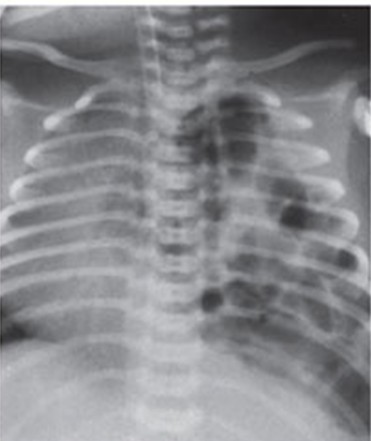

Q157. A 1-day-old newborn with significant respiratory distress is admitted to the ICU. A chest radiograph is performed. What is the most probable diagnosis based on the clinical and radiological findings?

- Congenital Pulmonary Airway Malformation (CPAM)

- Congenital Diaphragmatic Hernia (CDH)

- Congenital lobar emphysema

- Neonatal pneumonia

Answer: B